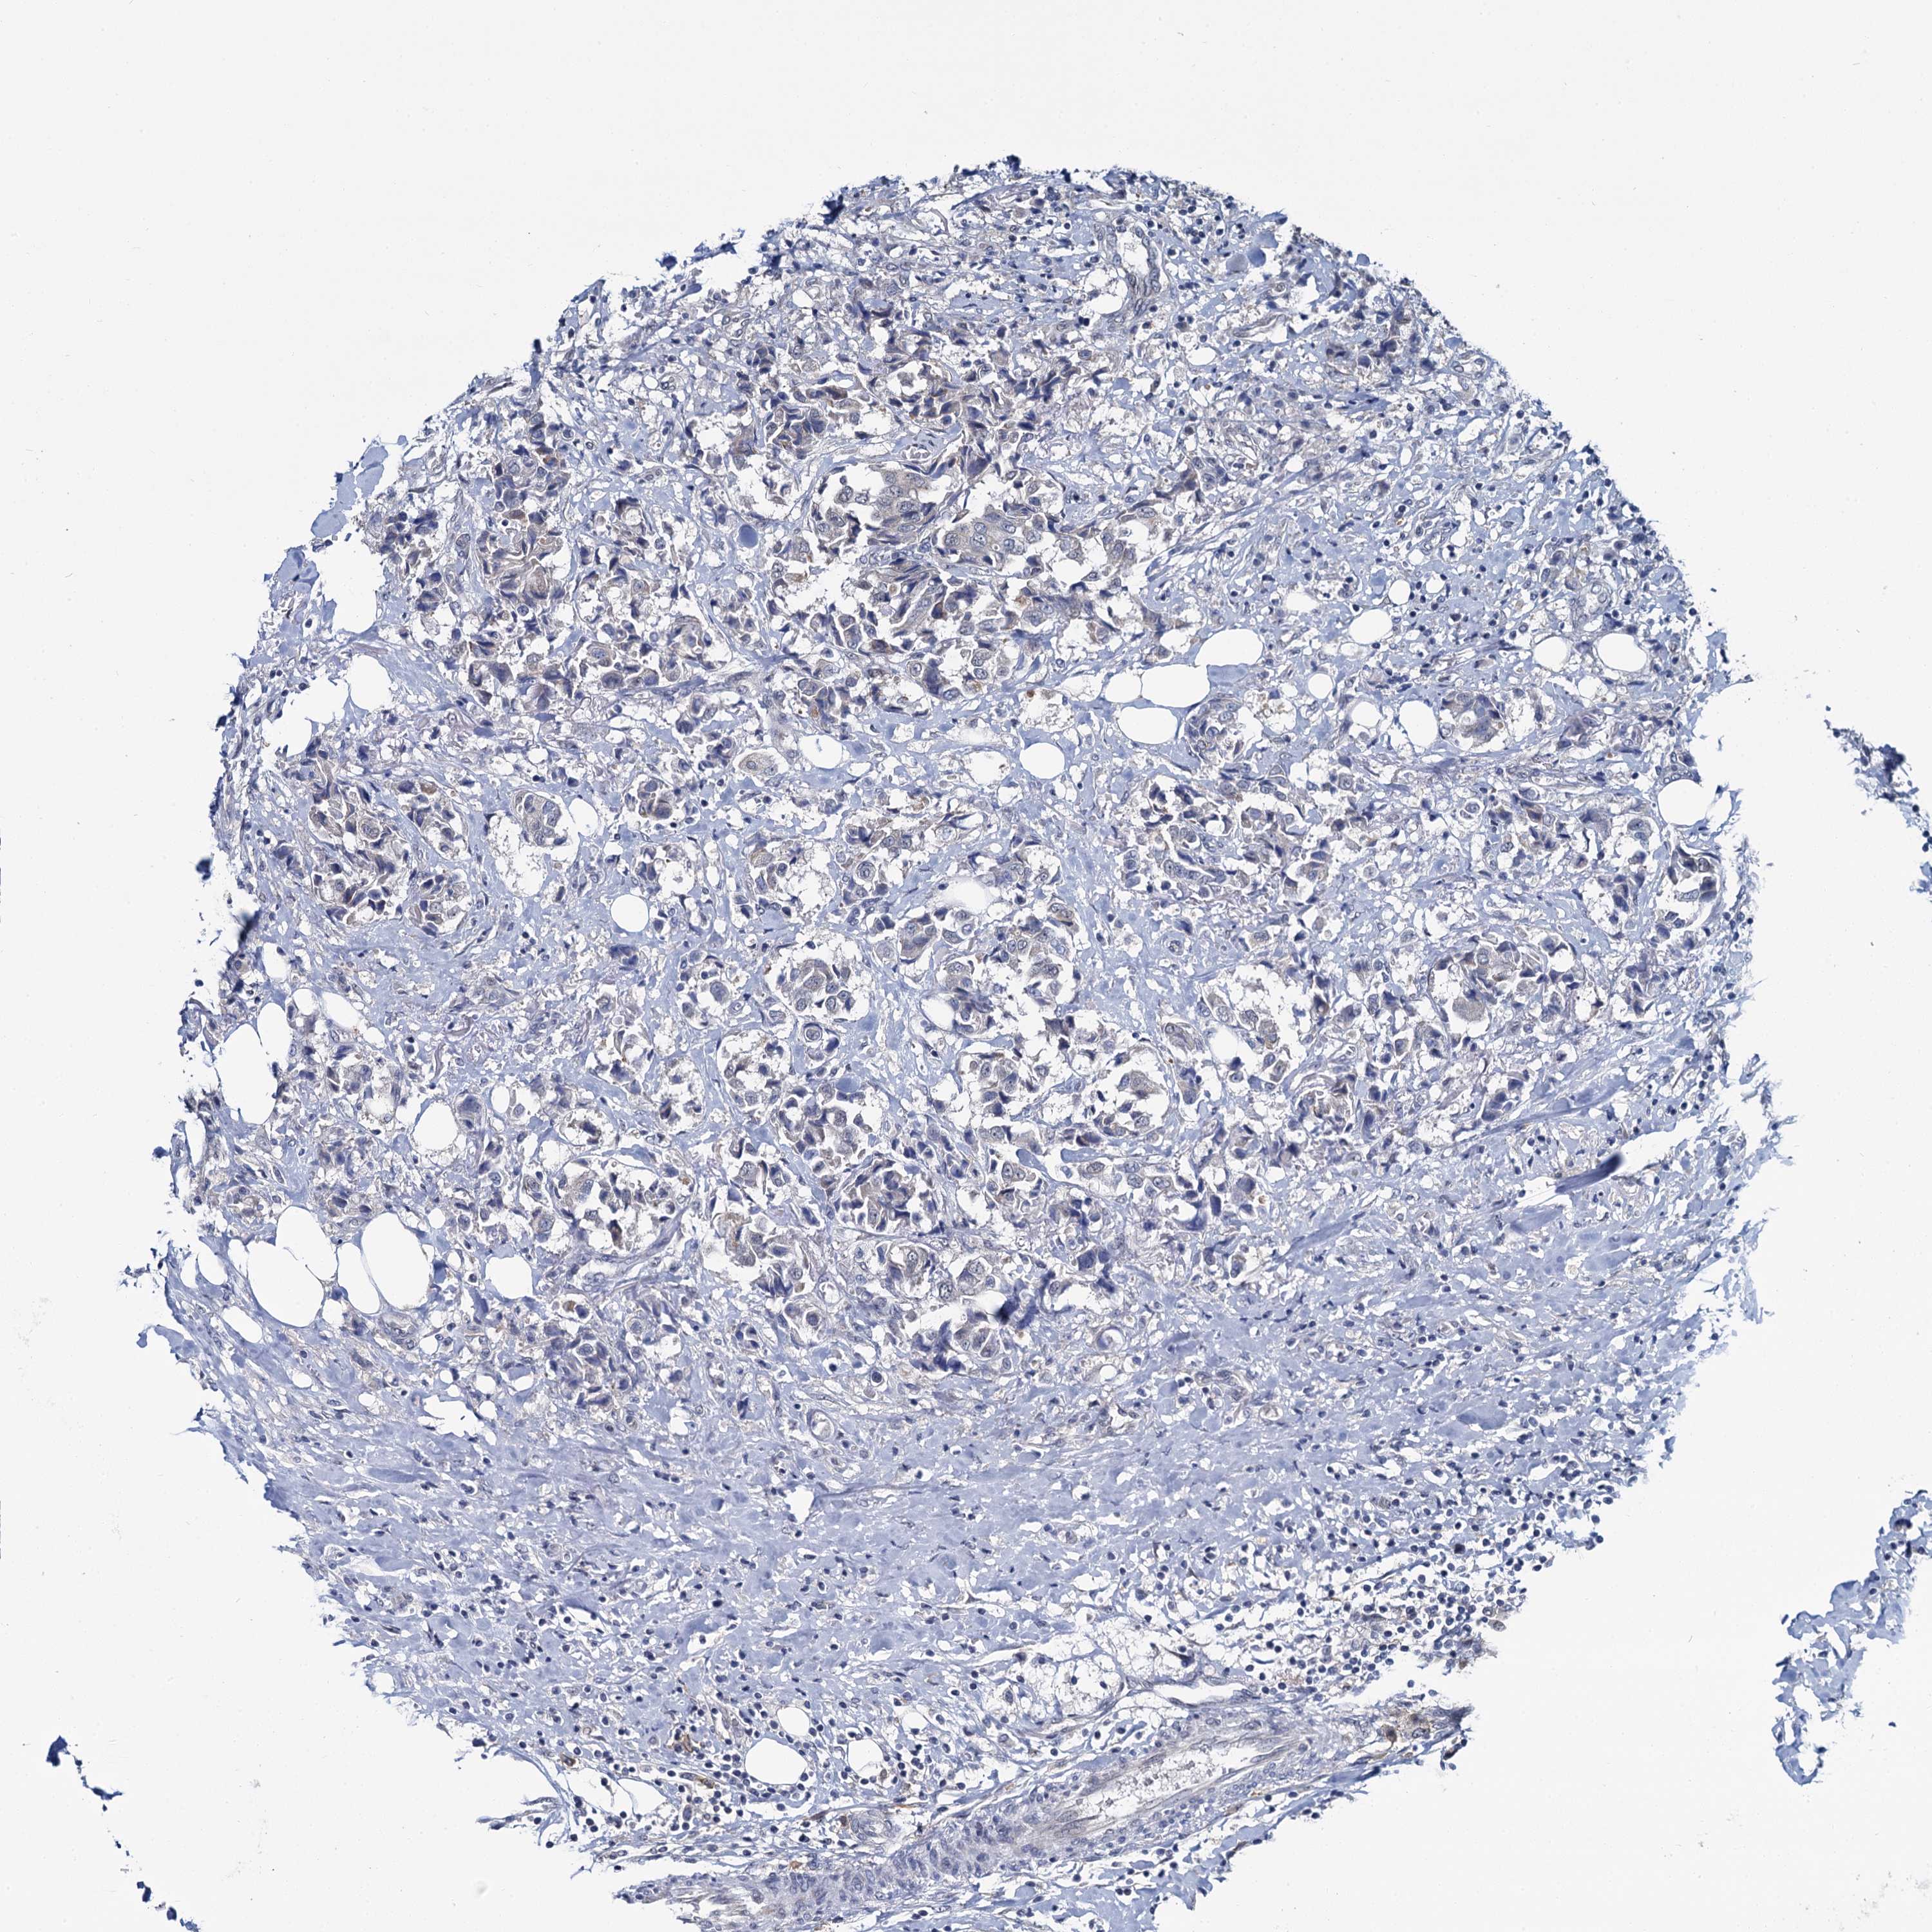

CANCER BREAST CANCER Show tissue menu

BRCA TCGA BRCA VALIDATION PROTEIN EXPRESSION